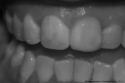

Estética

Cuando hablamos de estética no solo hablamos de belleza y armonía en las piezas dentales, sino de algo aún más importante: NATURALIDAD, tres conceptos íntimamente ligados.